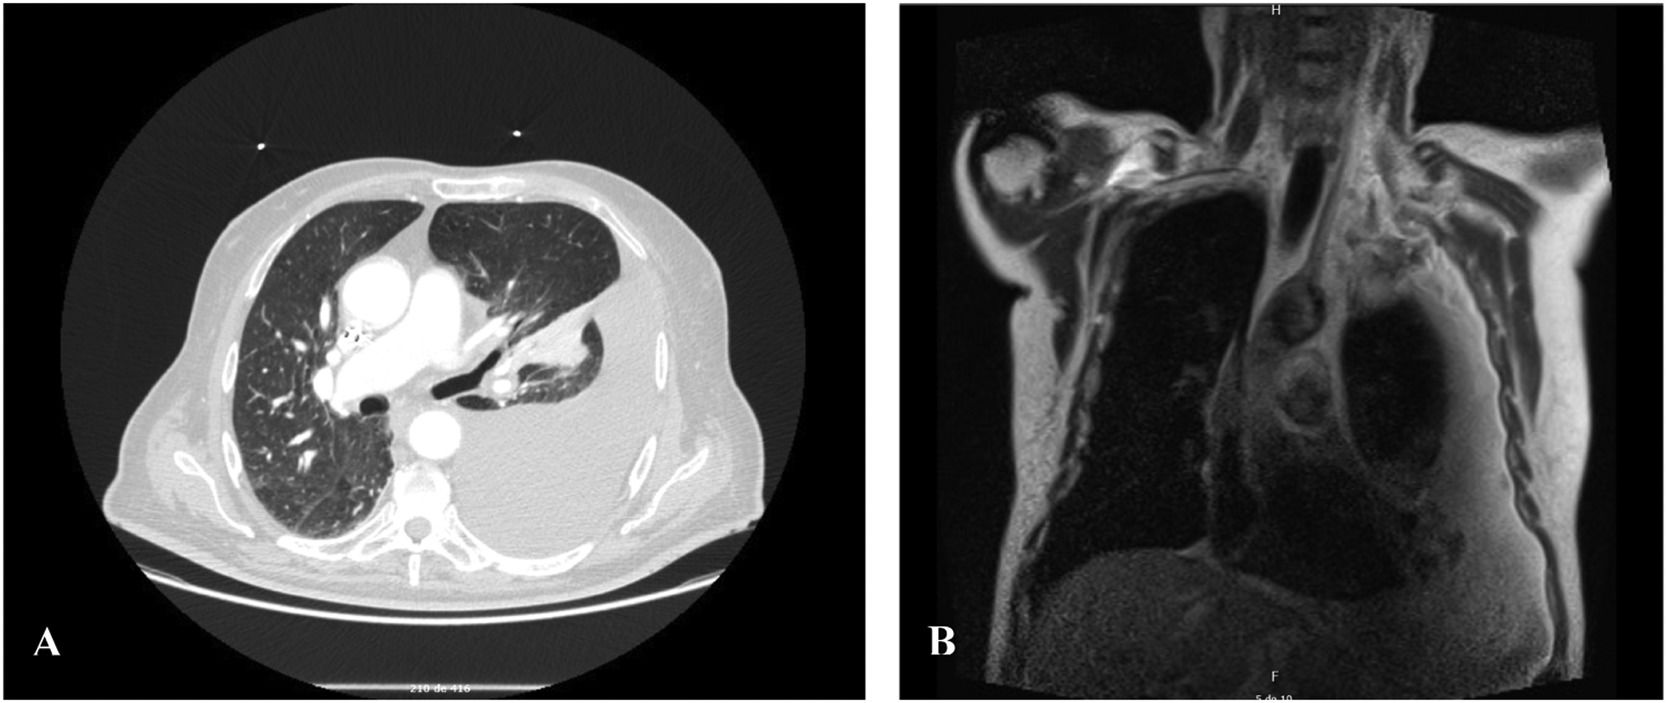

A 78-year-old male presented to our hospital with a large-volume and recurrent left pleural effusion. Cytologic examination of the effusion was negative for malignant cells. Routine haematologic, blood chemical and enzyme tests were within normal limits. Computed tomography (CT) (Fig. 1A) of the thorax revealed a mediastinal pleural mass associated with extensive pleural effusion on the left. Magnetic resonance imaging (MRI) (Fig. 1B) showed a solid, heterogeneous lesion in the mediastinal pleura, with well-defined limits and regular contours, measuring approximately 36 × 23 mm with the longest perpendicular axes. The lesion was mostly isointense on T1 and moderately hyperintense on T2, with central hypointense areas. Additionally, a lesion was identified at the level of the pectoralis major muscle sheath, measuring about 73 × 41 mm in the longest perpendicular axes. The two lesions, although undetermined by imaging, suggested the possibility of schwannomas. A biopsy of the lesion in the pectoralis major muscle sheath was performed, and the morphological and immunohistochemical findings were consistent with a diagnosis of schwannoma.